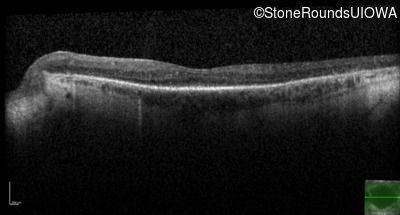

Optical Coherence Tomography - Left - 20/40 -2

Exemplar / OCT Stack